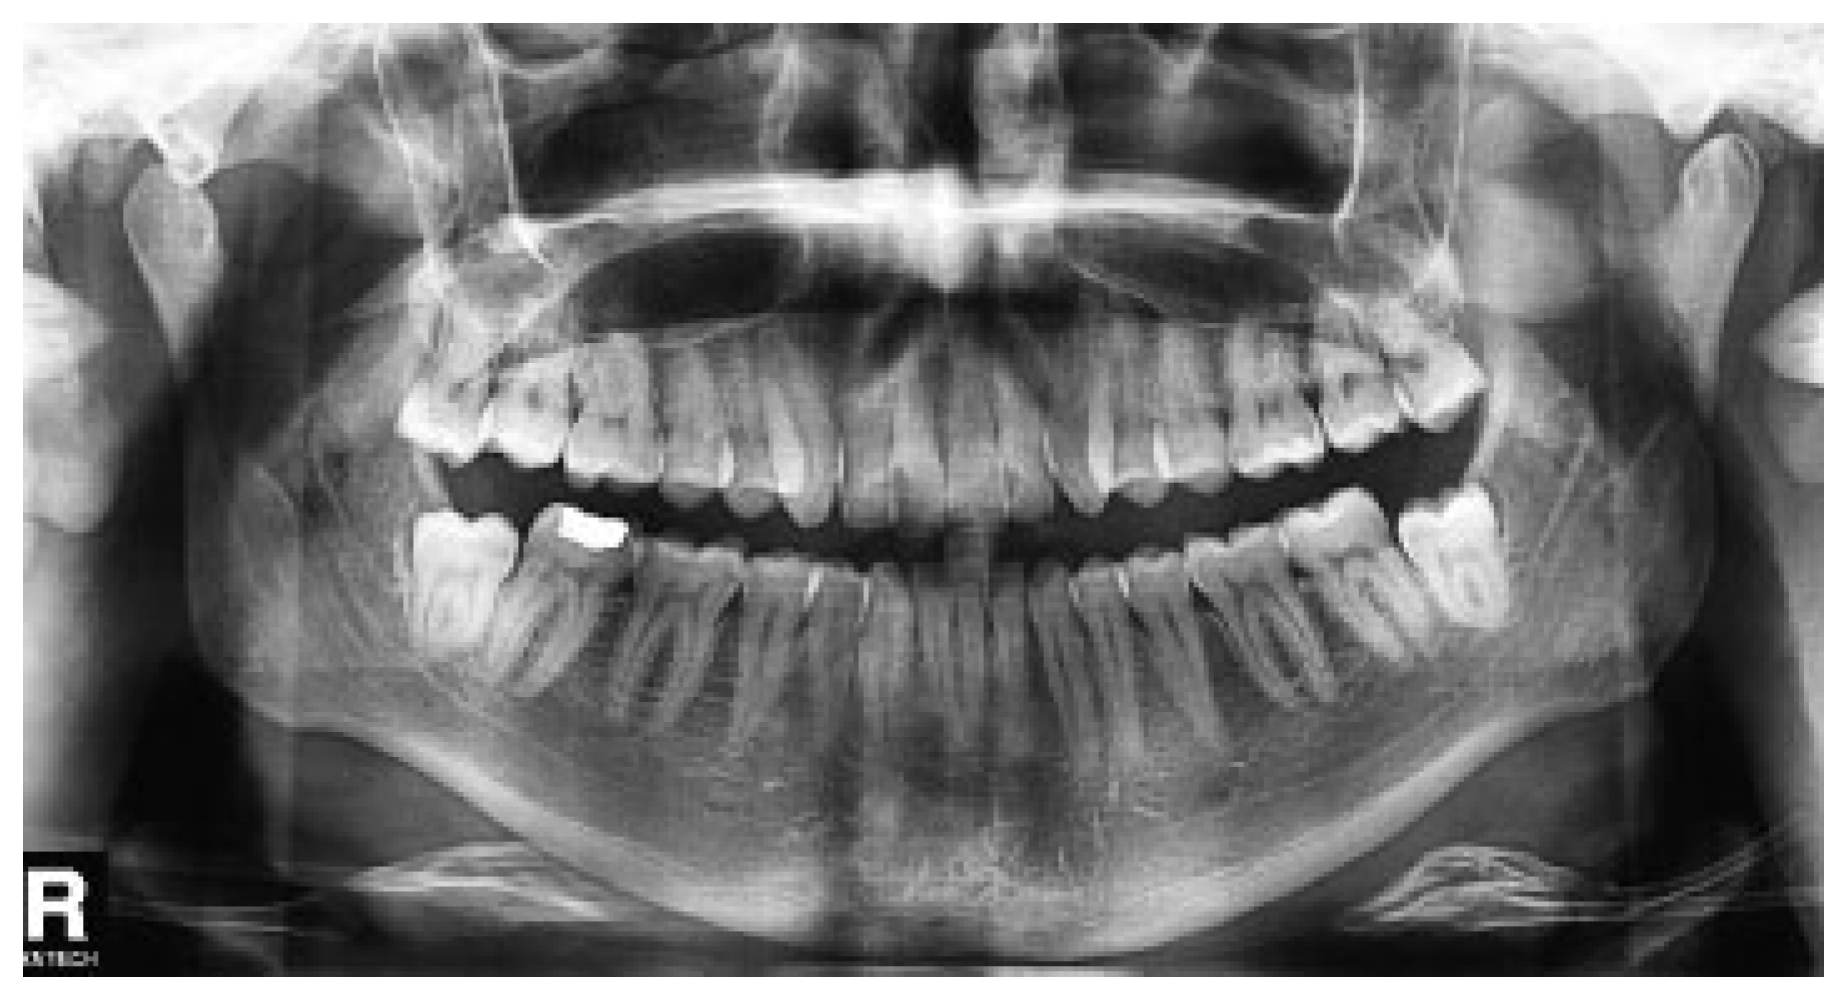

Case Report